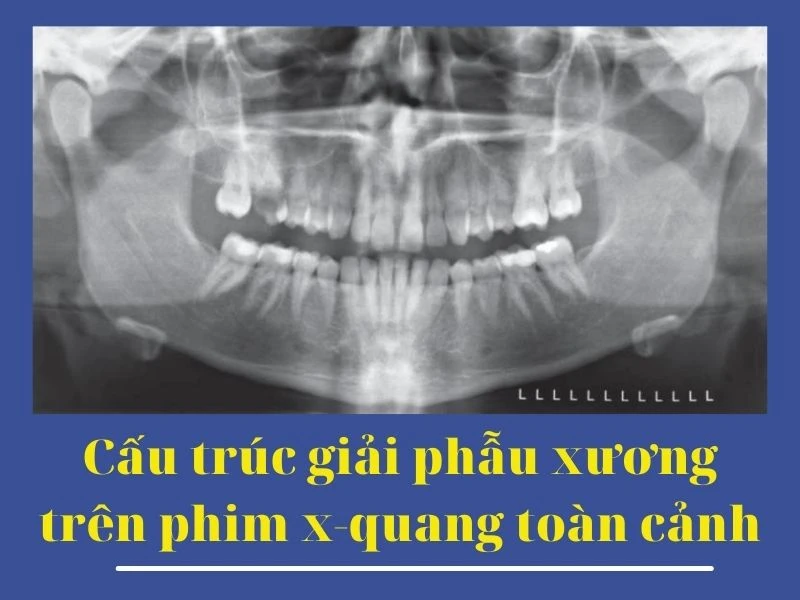

Hình 17. Cấu trúc giải phẫu xương hàm dưới trên hình ảnh phim x-quang toàn cảnh. Hình ảnh A và B là hai hình trùng lặp của cùng một bệnh nhân. 1, Lồi cầu xương hàm dưới. 2, Cổ lồi cầu xương hàm dưới. 3, Mõm vẹt xương hàm dưới. 4, Hình ảnh ma, mặt sau của bờ dưới hàm dưới bên trái. 5, Ống thần kinh xương ổ răng dưới. 6, Bờ dưới xương hàm dưới. 7, Hình chồng lên của bóng đốt sống cổ. 8, Lỗ cằm. 9, Hõm dưới hàm (chỗ lõm tại vị trí tuyến nước bọt lưỡi). 10, Góc hàm. 11, Gờ chéo ngoài. 12. Hõm xích ma.